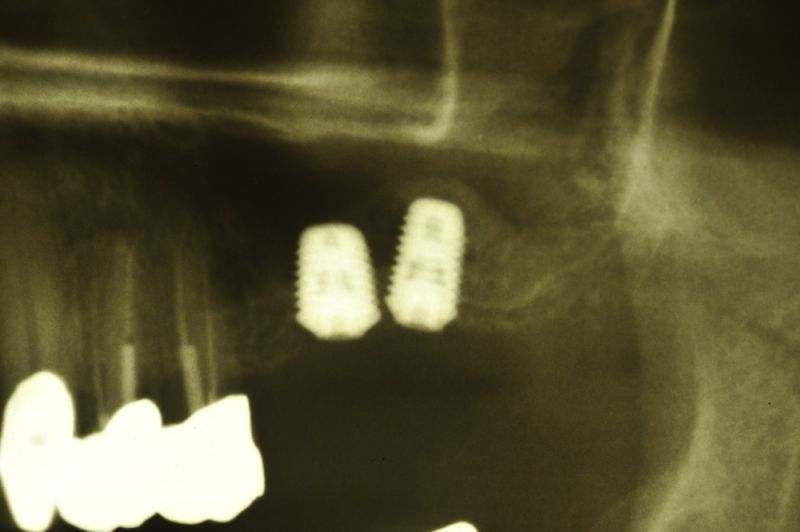

Am heutigen Tag sind in regio 26 und 27 zwei Implantate mit einem externen Sinuslift versorgt worden. Die Besonderheit des Eingriffs liegt darin, dass im Oberkieferseitenzahnbereich, bei einer noch vorhandenen Restknochenhöhe von wenigen Millimetern, zwei Implantate gesetzt und gleichzeitig eine Aufdoppelung des vorhandenen Restknochenangebots, durch die Schaffung eines Raumes zwischen knöcherner Abgrenzung der Kieferhöhle und der in die Kieferhöhle hinein verdrängten Kieferhöhlenmembran geschaffen werden konnte.

Nun wird die Membran vorsichtig in das eröffnete Ei hinein gedrückt. In die Eierschale wird an anderer Stelle, aber in der Nähe, nun ein zweites Loch gebohrt und in dieses Loch dann vorsichtig das Implantat hineingeschraubt. Das Implantat muss hierbei fest sitzen, oder wie man sagt: primärstabil! Ein Teil des Implantates ragt nun in das leere Ei hinein und zwar so, dass die verdrängte Membran des Eies sich wie eine Art Zirkuszelt über das Implantat hinweg spannt.

Der Raum, der nun zwischen dem Boden des Zirkuszelts und der Zirkuszeltspitze entsteht, der Mast, der das Zirkuszelt in der Mitte trägt, entsprich hier dem Implantat, wird nachfolgend mit einem Gemisch aus Knochen, Blut und Knochenersatzmaterialien aufgefüllt.

Genau das kann man dann auf dem Röntgenbild erkennen. So bildet sich innerhalb der Kieferhöhle, aber begrenzt durch die Kieferhöhlenmembran, neuer Knochen, der dann nachfolgend dem Implantat den knöchernen Halt gibt, den es unter späterer Belastung durch Kaudruck benötigt.

Wenn man so will, ermöglicht das Implantat, das wie ein Mittelmast das Zirkuszelt in die Höhe drückt, erst die Möglichkeit, dass der Hohlraum, der dann zwischen dem Zirkuszeltboden und der Mastspitze entsteht, sich nachfolgend mit Knochen auffüllt, so dass das Implantat am Ende des Einheilungsprozesses in voller Länge in neu gebildetem Knochen steht!